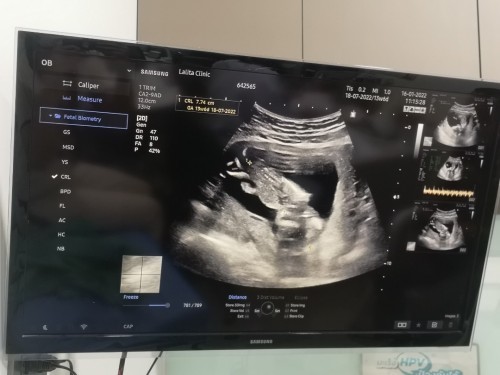

ตอนนี้15วีคคุณหมอบอกว่าน้องแข็งแรงปกติดี แต่คุณหมอแนะนำให้ไปตรวจดาวน์อันนี้ปกติไหมคะสอบถามผู้รู้ ท้องแรกค่ะ ภาพคือน้องตีลังกาอยู่น่ะค่ะ😁

ตีลังกาเหมือนกันเลย